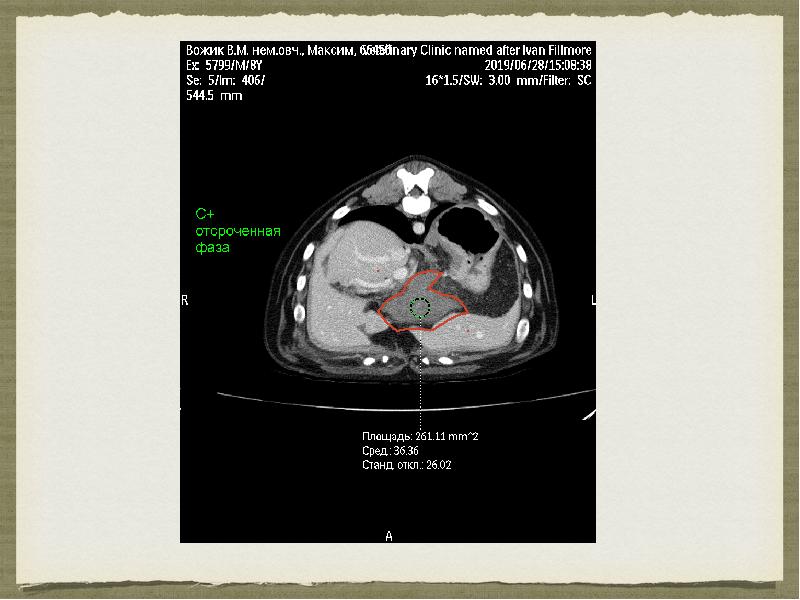

- 11. Компьютерная томография